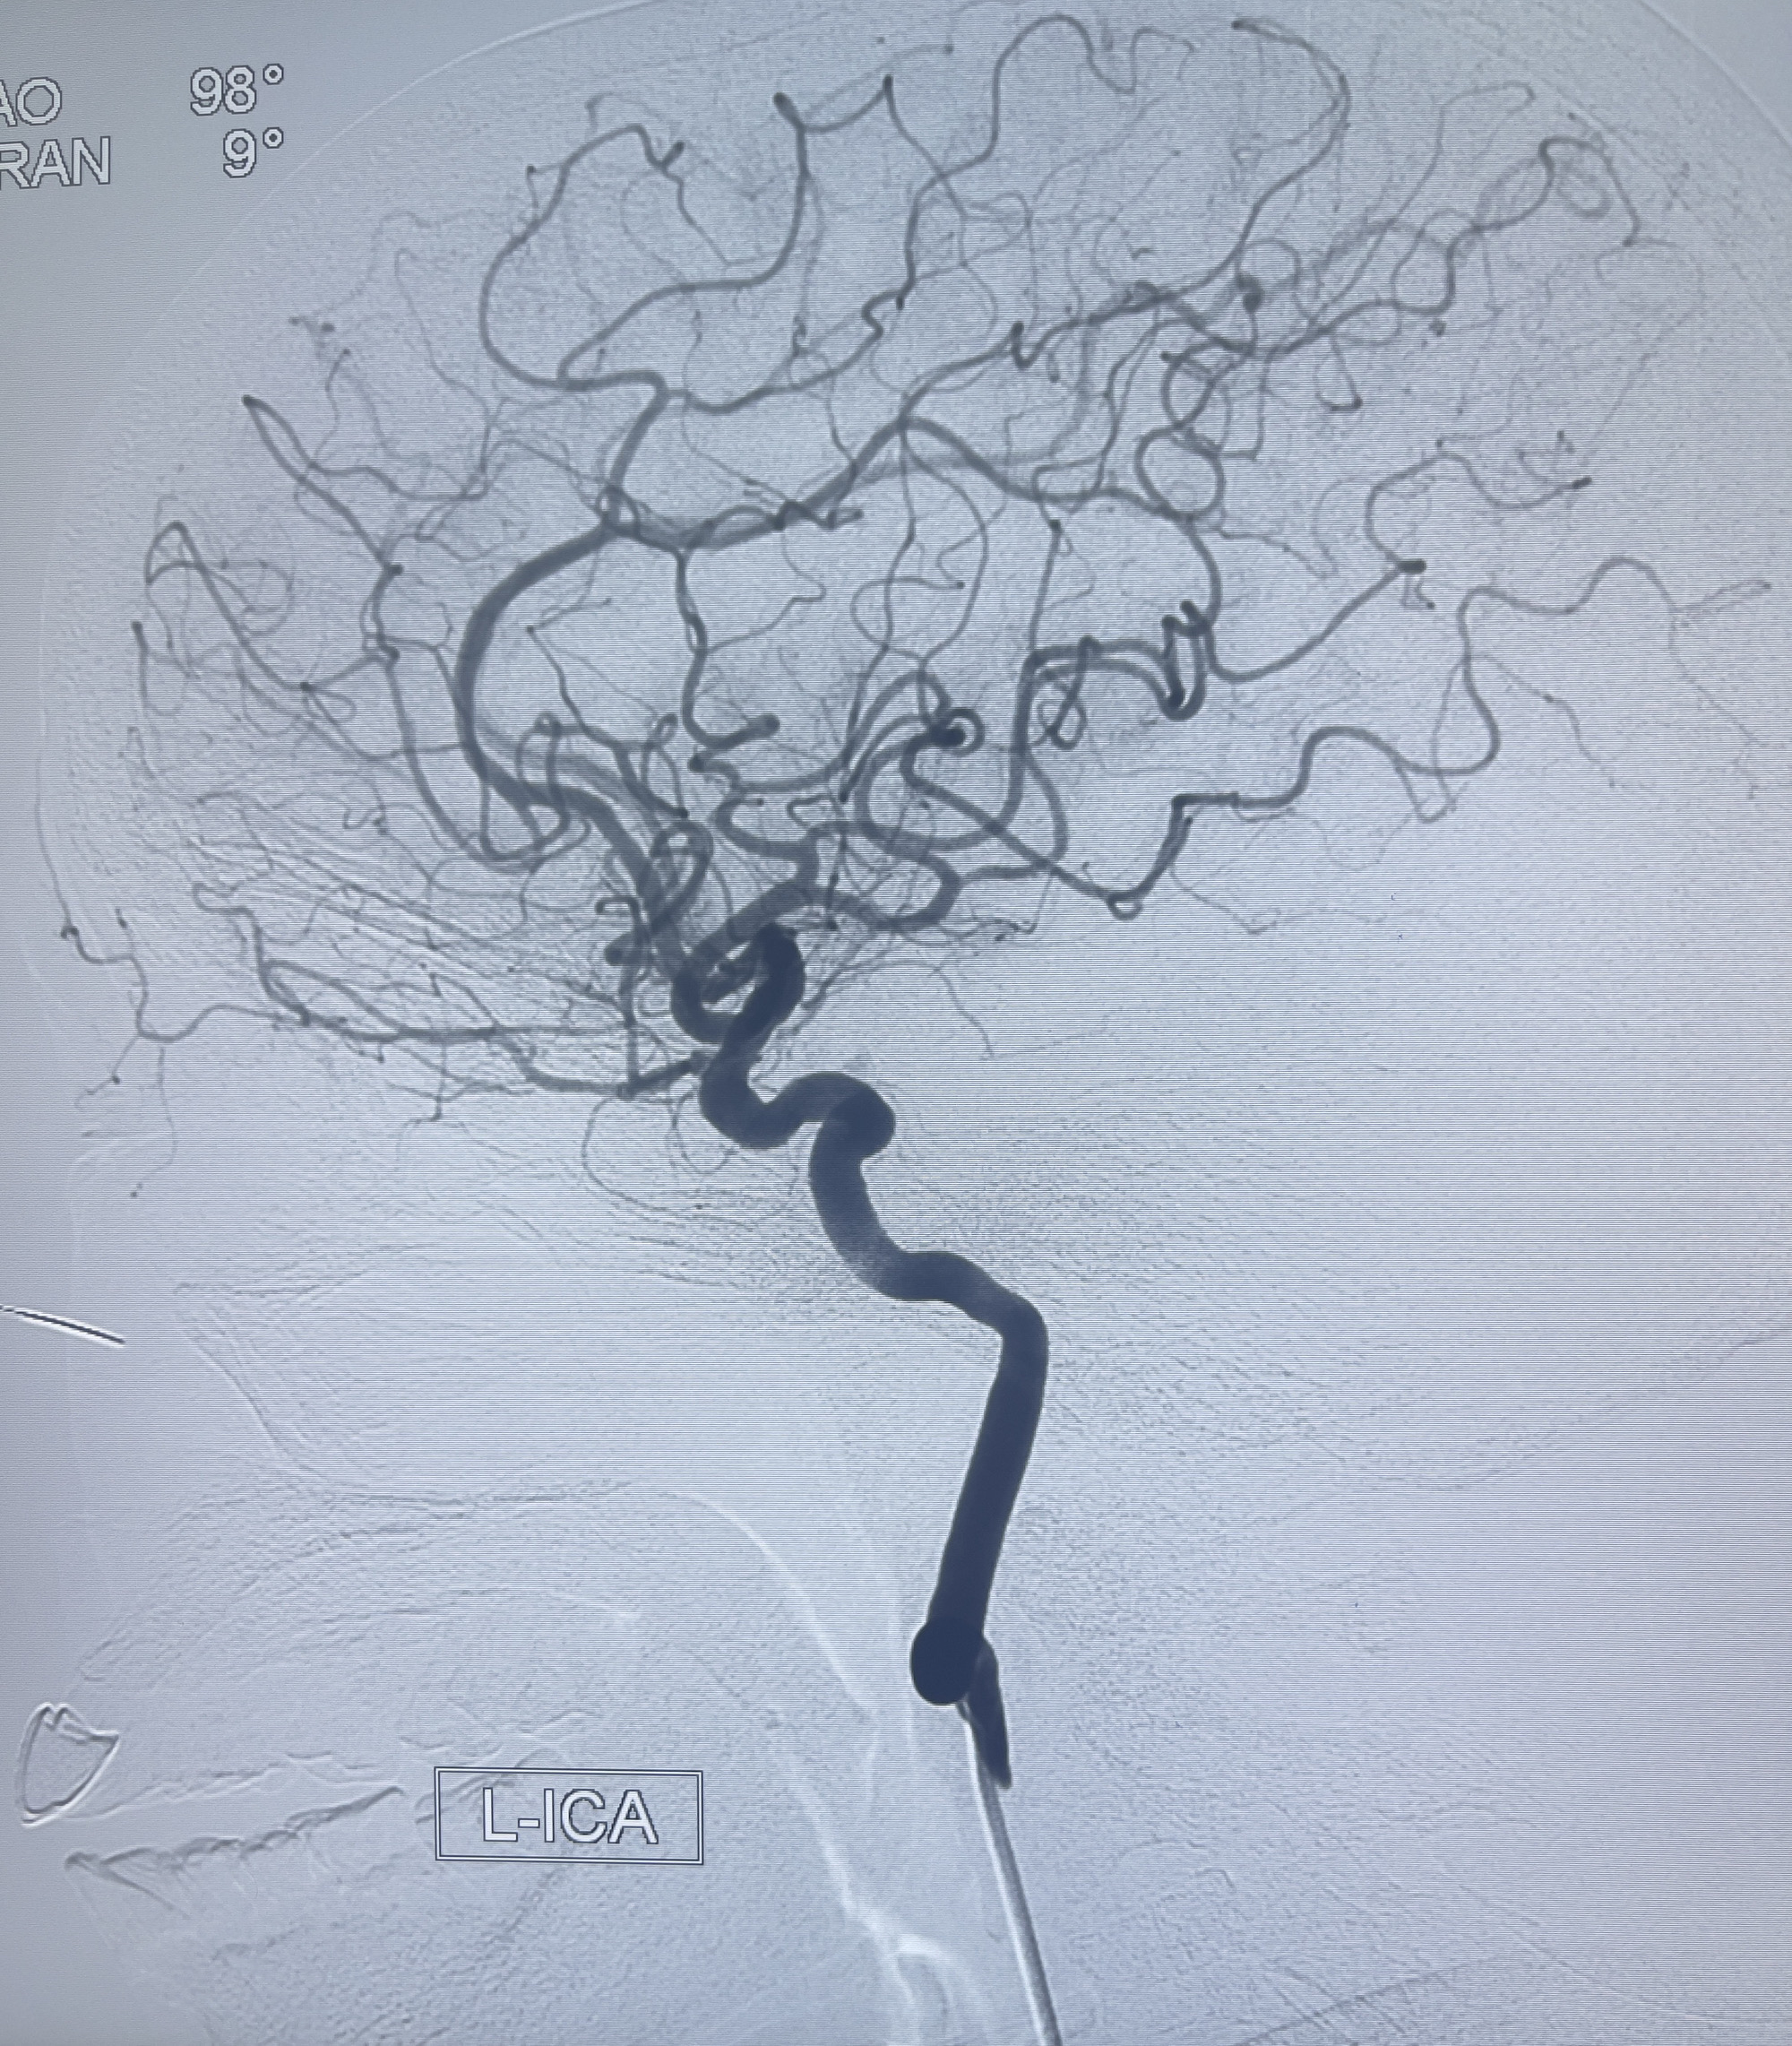

202.04.28脑血管造影:右侧大脑后动脉远段闭塞,右侧椎动脉V4段可见“囊状造影剂填充影”,大小7.64*7.65mm,可见PICA由动脉瘤发出;